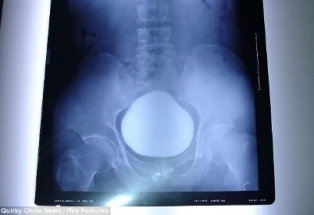

Ảnh chụp X-quang thấy rõ cục sỏi khổng lồ. Ảnh: Chinanews.

Bệnh nhân họ Trương, 43 tuổi, được đưa tới bệnh viện thành phố Vũ Hán để khám sau khi ông than thở rằng việc tiểu tiện ngày một đau đớn và khó khăn.  Các nhân viên y tế đã tiến hành chụp X- quang cho ông và họ đã sửng sốt khi phát hiện một vật thể khổng lồ rộng 11 cm nằm gọn trong bàng quang của bệnh nhân. Bác sĩ trưởng khoa phẫu thuật tiết niệu Ngô Thiên Bằng cho biết đây là viên sỏi bàng quang lớn nhất từ trước đến nay mà ông đã từng nhìn thấy, đồng thời cũng là viên sỏi nặng thứ hai được ghi nhận ở Trung Quốc cho đến thời điểm này. Viên sỏi bàng quang nặng nhất Trung Quốc, cũng là nặng nhất thế giới, được phẫu thuật lấy ra khỏi bàng quang của một phụ nữ nông dân tên Hứa Thủy Liên (40 tuổi) cũng ở tỉnh Hồ Bắc vào năm 2009. Nó nặng hơn gấp đôi viên sỏi này với khối lượng không thể tưởng tượng...2,4 kg.